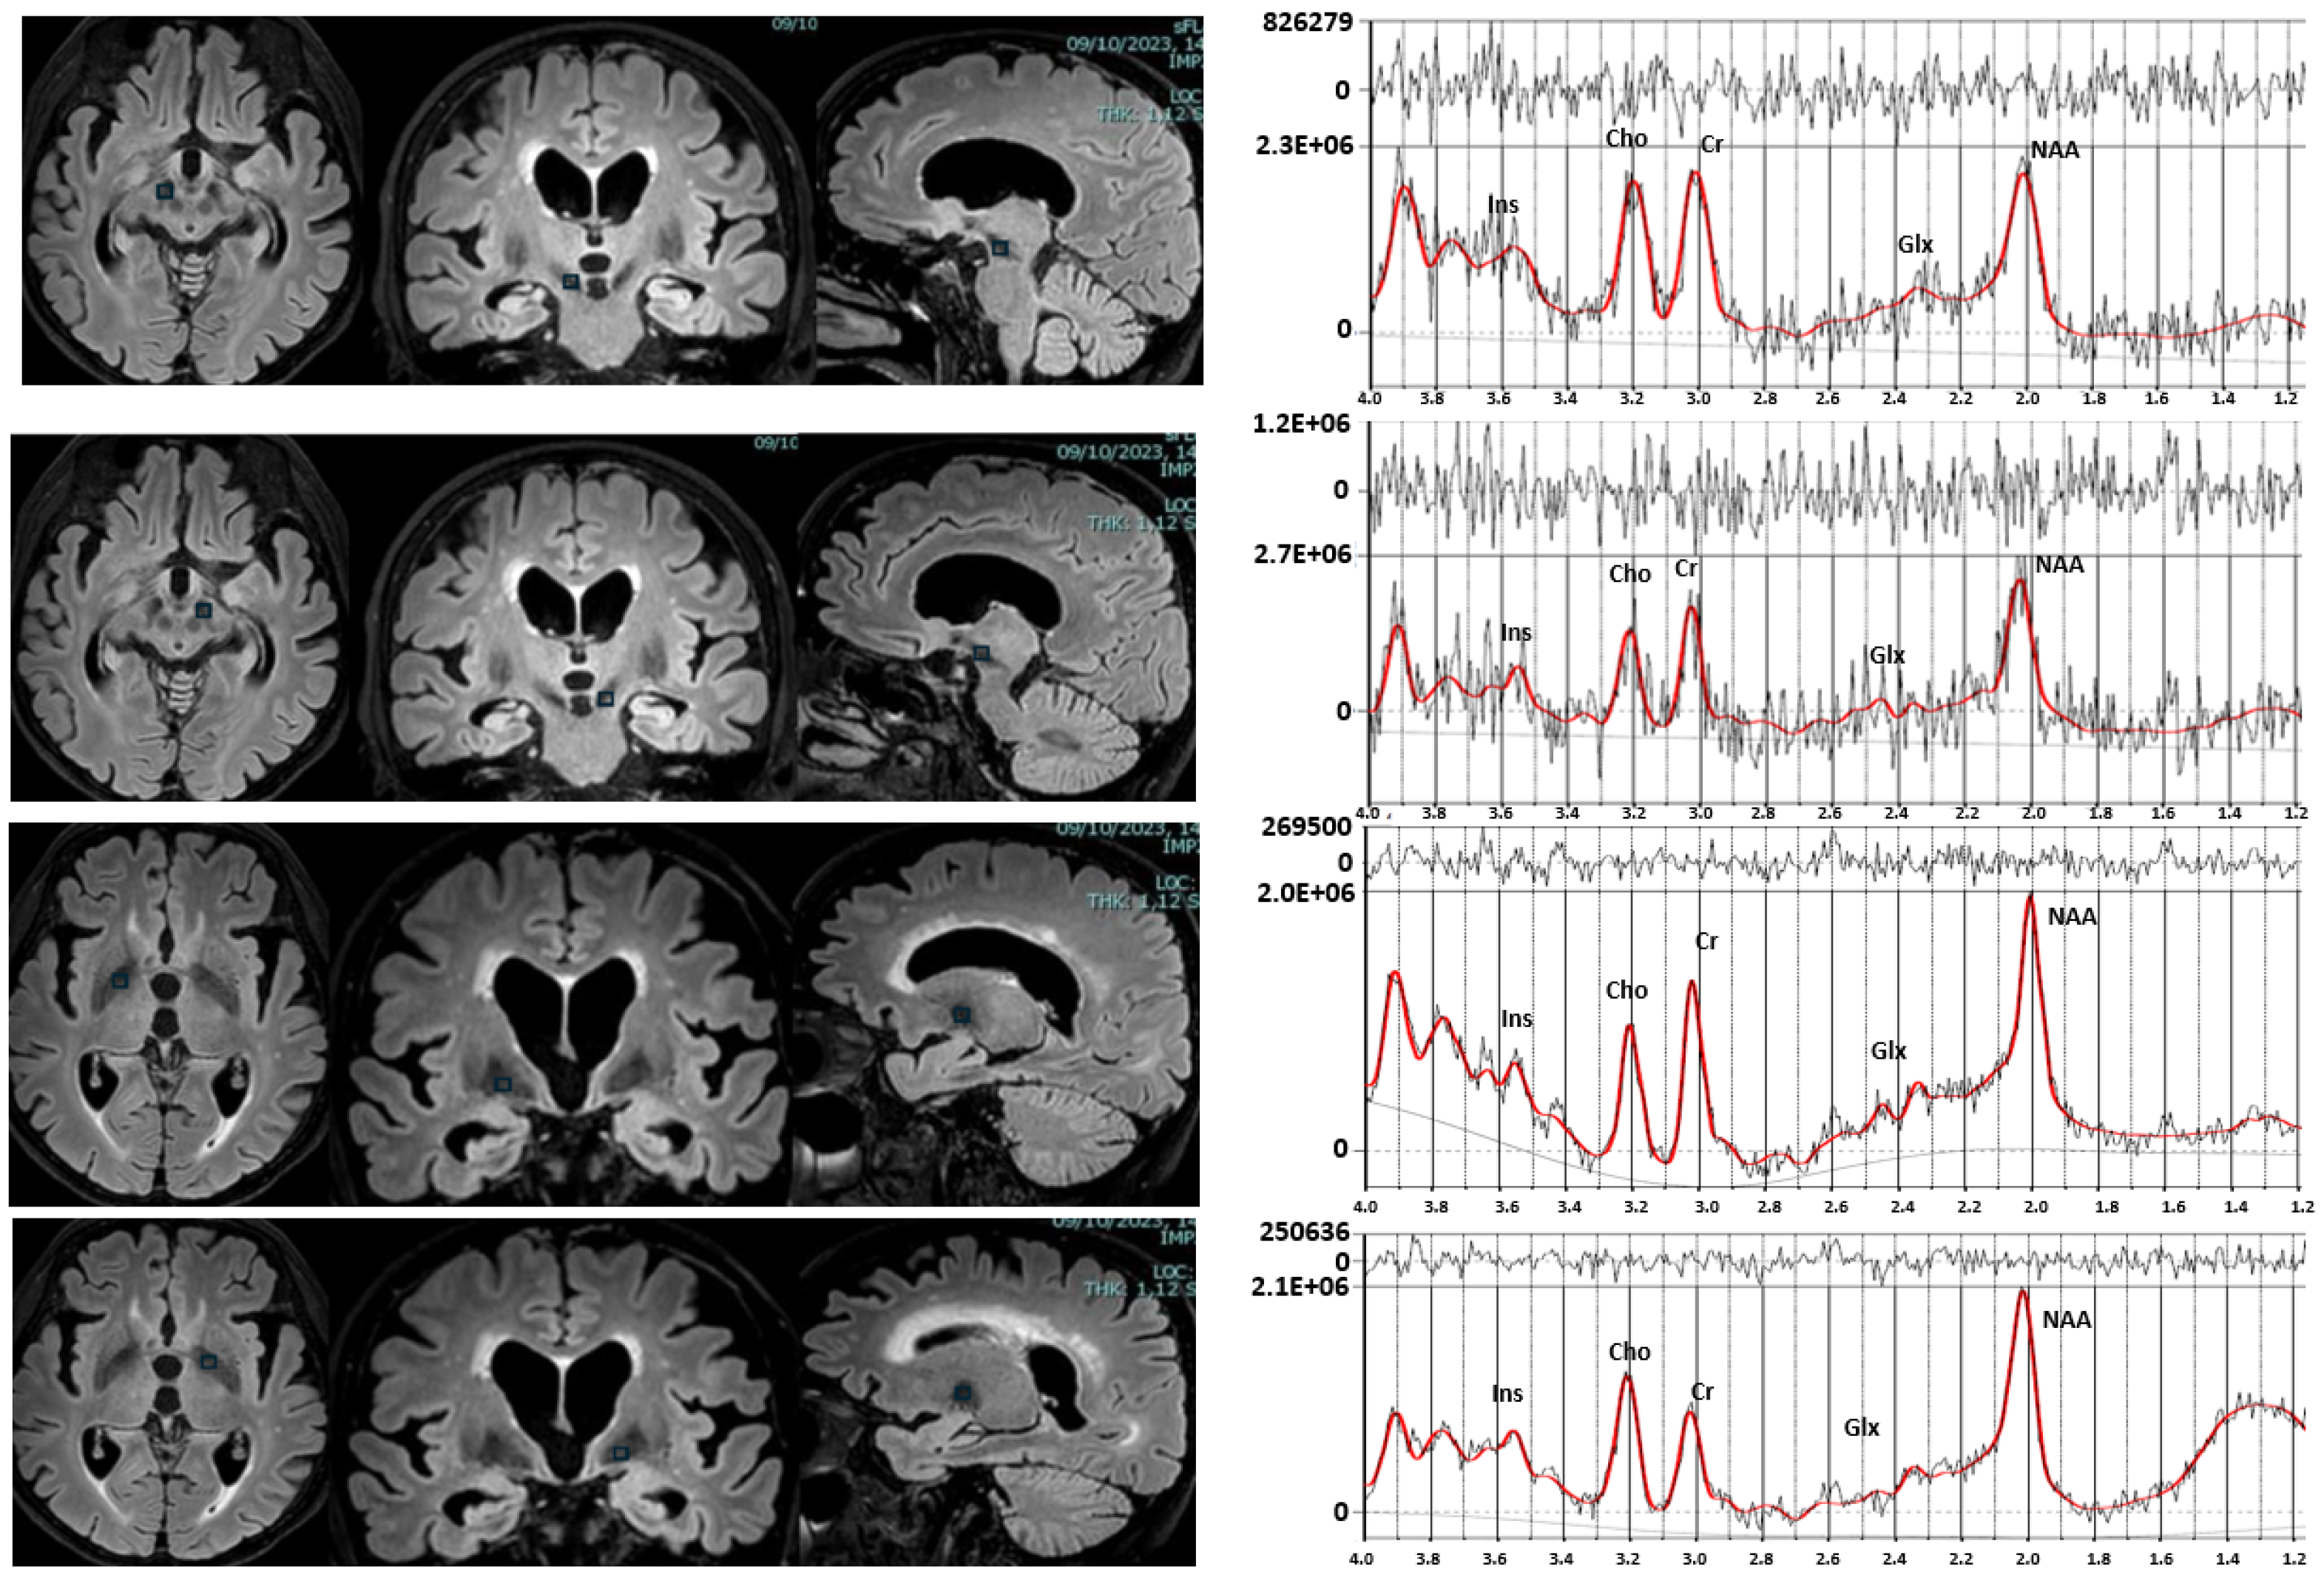

4.3. 1H-MRS Acquisition and Analysis